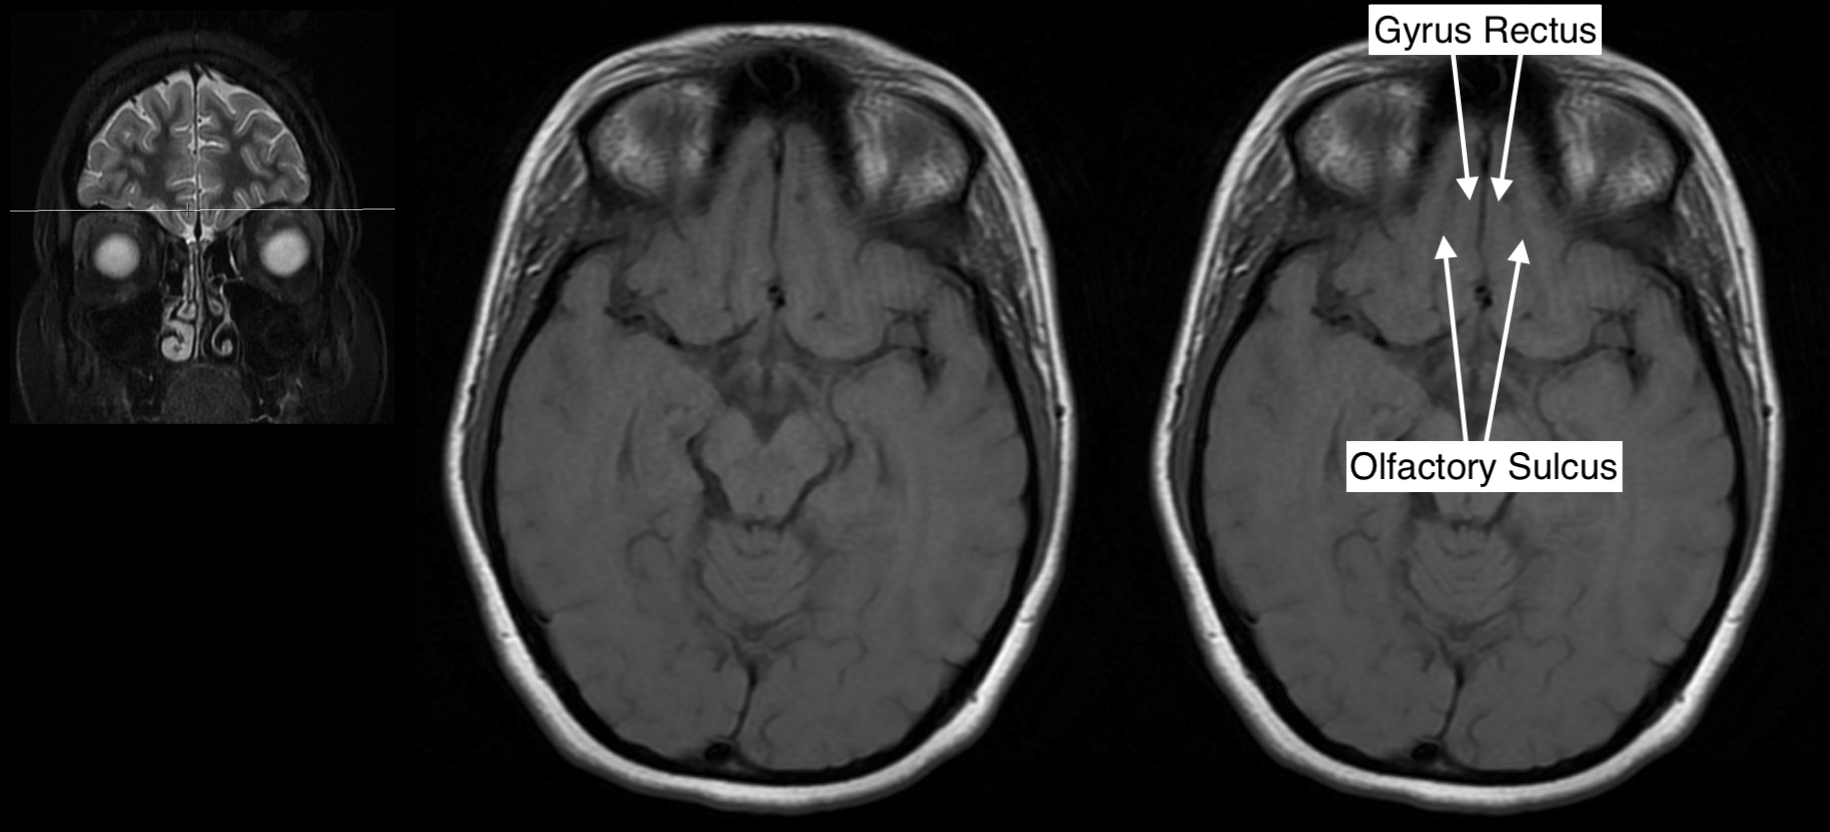

Radiological Anatomy Gyrus Rectus Stepwards Brain Gyrus Labeled Mri The main indications for tailored. We shall also explore the anatomy of the 12 pairs of cranial nerves and anatomic variants without pathologic significance, relying mainly on. Brain mri with annotations of major structures. The anatomy of the brain is studied by means of axial, coronal and sagittal views. A review of brain magnetic resonance imaging (mri) is used as. Brain Gyrus Labeled Mri.

Radiological Anatomy Gyrus Rectus Stepwards Brain Gyrus Labeled Mri Explore our video tutorial, quizzes, articles and labeled diagrams on this topic. The superior frontal gyrus is the medial most gyrus of the frontal lobe's superolateral surface, running from the frontal pole anteriorly,. The main indications for tailored. Brain mri with annotations of major structures. A review of brain magnetic resonance imaging (mri) is used as support. Mri is the. Brain Gyrus Labeled Mri.